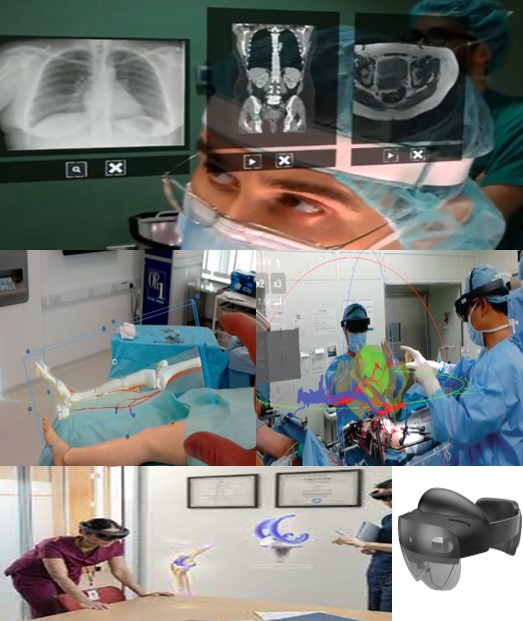

НАВІГАЦІЙНА СИСТЕМА ДОПОВНЕНОЇ РЕАЛЬНОСТІ HOLOLENS 2

Навігаційна система доповненої реальності Microsoft HoloLens 2 використовує комбінацію відстеження погляду, жестів рук та голосових команд для інтуїтивного керування голографічним контентом у реальному просторі. Вона накладає голографічне 3D зображення що генерує комп’ютер на навколишній світ, дозволяючи взаємодіяти з 3D-моделями, як у реальному житті, наприклад, масштабуючи їх жестами або переміщуючи поглядом. Це автономний пристрій з вбудованим процесором і операційною системою, який також інтегрується з хмарними сервісами, такими як Azure, для розширення можливостей.

Основні аспекти навігаційної системи HoloLens 2:

- Інтуїтивне керування: Користувач керує голограмами за допомогою природних дій:

- Жести рук: Рух рукою дозволяє маніпулювати об’єктами, наприклад, збільшувати їх або переміщувати.

- Відстеження погляду: Пристрій відстежує, куди дивиться користувач, що дозволяє вибирати та взаємодіяти з елементами голографічного інтерфейсу.

- Голосові команди: Можна використовувати голосові команди для виконання певних дій або команд, що в поєднанні з жестами забезпечує більш повний контроль.

- Нативна взаємодія з реальністю:

- Голографічні об’єкти накладаються безпосередньо на навколишнє середовище, а не замінюють його повністю, як у VR.

- Користувач може переглядати голограми під різними кутами, нахиляючи голову.

- Технологічна основа:

- Автономний пристрій: HoloLens 2 працює самостійно, без підключення до зовнішніх комп’ютерів, завдяки вбудованим процесорам і операційній системі Windows.

- Хмарна інтеграція: Пристрій може працювати як клієнт для даних, що зберігаються в хмарі Azure або в інтернеті.

- Переваги для бізнесу та промисловості:

- Пристрій призначений для корпоративного використання, пропонуючи інноваційні рішення для спільної роботи, дизайну та технічного обслуговування.

- Покращений комфорт і ергономічний дизайн сприяють тривалому використанню.

Вдосконалення навігаційних систем у лабораторії медичної інженерії дозволяють скоротити час проведення операції, що в свою чергу зменшує крововтрату та перебування пацієнта під наркозом, зменшує ризики отримання ускладнень.